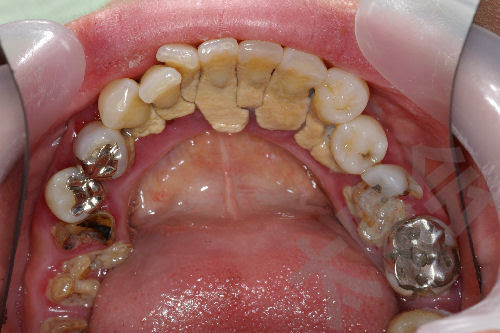

茶色に色が付いた歯は虫歯では? 歯と歯茎の間が茶色くなったときに考えられる一番の原因は、磨き残しが固く石灰化する歯石です どんなに丁寧に歯磨きしているつもりでも少しずつ残ってしまう磨き残しが石灰化したものが歯石ですが、歯石になると 外から帰ってきたら、 ごはんを食べたら、 歯みがきの時に、 誰もがしたことのある、うがい。 冬も近いということで、風邪予防に手洗い・うがいを意識し始める季節ですね。 うがいをする時は、何を使っていますか? うがいと一口に言っても、方法は様々。 定番なのは水でのうがいです 歯石が付着しないようにするためには、日頃から歯垢をきちんと取り除かなければいけません。 23 唾液が作られる器官の出口は歯石が付着しやすい 歯石が付きやすい場所は「下顎の前歯の裏側」や「上顎の奥歯の頬側」といわれています。

これは「歯石」であることが多いです。 色になっているのを発見し、驚かれて来院されることがあります。また「3歳頃では奥歯が生えてきて、頬側や舌側がオレンジ色になっているんですがこれは何ですか? (3)歯が生えてきたときから黄色〜茶色 巨大歯石の大きさ 歯石が成長しやすいのは、下の前歯の裏、上の奥歯の外側などです。 これは唾液が出てくる穴があるため、常に唾液のリン酸カルシウムが吹き付けられているようなものだからです。 プラークが歯石になっても、初期の段階であれば

②歯垢、歯石 歯垢、歯石が歯の根元につく事で、明るさに重要な光を遮断してしまう為、歯が黄ばんでみえてしまいます。 ☆対策・・・歯垢や歯石は歯周病の原因の1つにもなります。まず歯石がついてしまったら必ず除去することが必要です。自分では落とせない!手強い歯の変色 Top3 目立って落ちない歯の着色が気になることはありませんか? 気にする必要が無いものから、すぐに治療した方が良いものまで、診療時にもよく見かける落ちない歯の着色のTop3について紹介します。歯石予防には、歯垢のうちに確実に落とすことが大切です。 もし歯石がついてしまったら、早めに歯科医院へ。 日ごろから定期的に検診を受けて、歯石をチェックしてもらうといいでしょう。 歯の役割としくみ 唾液の働き かむことの大切さ 歯垢と